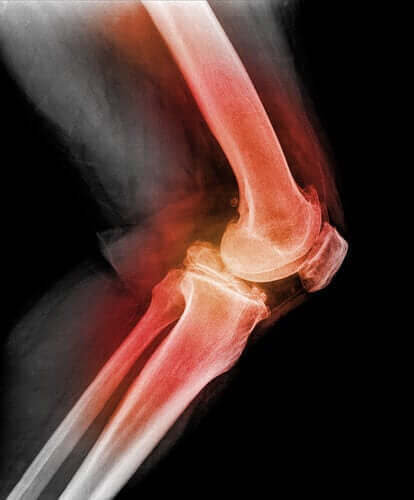

Pour établir le diagnostic d’une luxation de la rotule, le médecin doit palper le genou, tenter de le plier le genou et le faire bouger dans différentes directions. Le recours aux radiographies, à la résonance magnétique (RM) ou à une tomographie assistée par ordinateur permet de voir des images de la luxation de la rotule et de toute autre lésion du genou.